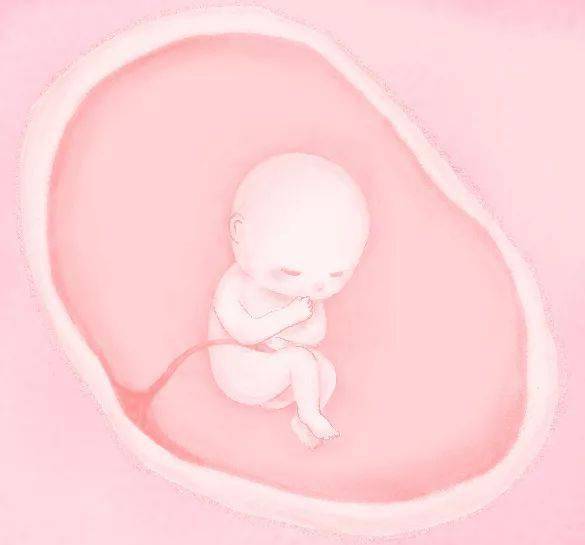

▲ 孕 3 月

90%的器官已经形成,正在发育;头显得格外大胎儿增长速度加快,对外界刺激的反应增强,上颚开始生成,胎儿各器官基本已经发育完成,胸腹腔分开, 手指和脚趾都发育了,可以看到胎儿在动。